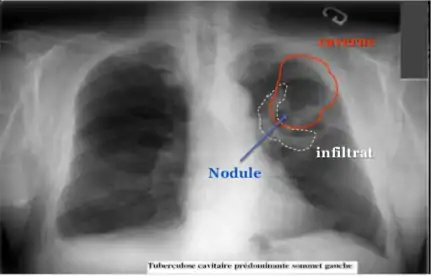

Diagnostic radiologique

La modalité de diagnostic radiologique se révèle très utile et indiquée comme étant un examen de première intention en cas de tuberculose pulmonaire et ostéoarticulaire[77]. Cela est justifié par les images radiologiques plus ou moins spécifiques à la tuberculose. La littérature rapporte que la spécificité varie de 27 à 81 % selon l’étude. Les imageries idéales et révélatrices de la tuberculose répondent à certains attributs dont le premier est lié au siège. En raison de l’affinité que les BK ont envers les régions aérées, la lésion radiologique est souvent observée dans les parties hautes des poumons. Néanmoins, l’image radiographique peut contenir différentes formes :

- infiltrat : traduisant des lésions débutantes de l’infection via une opacité peu dense, hétérogène et étendue ;

- nodule : granulome de taille variable, isolé ou groupé ;

- tuberculome : nodule isolé pseudotumoral ;

- caverne : excavation par perte de substance au sein d’un infiltrat, aux parois épaisses.